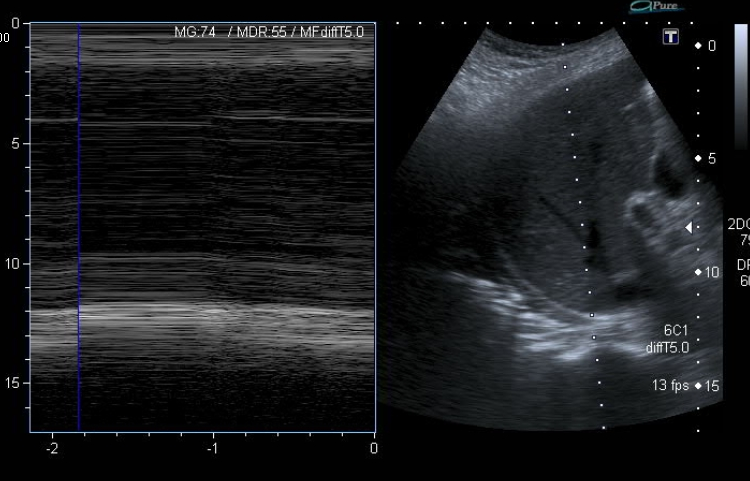

Ecografía diafragmática: se identifica una marcada elevación del hemidiafragma derecho, que se encuentra aplanado con los movimientos respiratorios (imagen 3 y 4) en modo M, compatible con parálisis diafragmática. No se visualiza líquido en fosa de Morrison. El hemidiafragma izquierdo se encuentra normoposicionado con movimientos normales y acordes a la respiración.